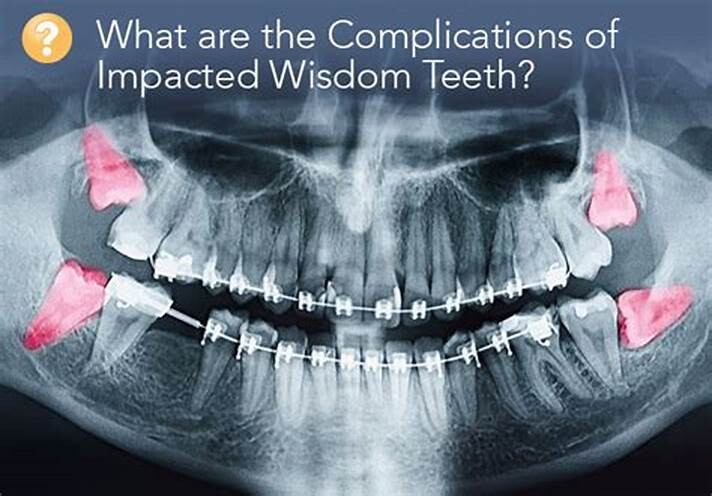

What Are the Dangers of Not Removing Wisdom Teeth?

Any type of surgery is scary, and it is natural for people wanting to postpone the surgery as long as possible. Similar is the case with a dental procedure, it can be daunting too. You might be postponing due to various reasons – as you will have to encounter wisdom teeth removal cost, you might have to avail a day’s leave for the procedure, and above all you are frightened!

But, this delay can be really dangerous and can have serious consequences on your health. Here are a few reasons as to why delaying the wisdom teeth removal can be a bad idea:

Wisdom teeth promotes Gum Disease

It is a challenging task to clean the area in which the third molars have erupted. Therefore they are at a greater risk of acquiring the periodontal problems. The gum diseases are usually caused by bacteria, and when a tooth can’t be precisely cleaned on a regular basis, the dental plaque gets accumulated around the tooth, which may lead to further complications.

Formation of Cysts or Tumours

If the wisdom teeth problems are not dealt in an appropriate manner, the tooth will develop a sac within the jawbone. This sac has the ability to fill with fluid, which gradually develops into the formation of cyst, damaging the teeth, jawbone, and nerves. There are chances that this cyst could progressively develop into a tumour if untreated which could ultimately result in the removal of tissue and jaw bones.

Mutilates the Neighbouring Teeth

Since there is not enough room for the tooth to grow, it will case the teeth to grow in an abnormal manner. This results in impaction of the teeth, giving rise to many other oral problems. When the wisdom tooth emerges against the second set of molar, it might damage them, increasing the risk of acute infection. It will also have an effect on other teeth, which will intensify the need for an orthodontic treatment to align the other teeth.

Tooth Decay

The fully impacted or the partially impacted wisdom teeth are at greater risk of tooth decay, than other teeth. This usually happens, because of the location of the wisdom tooth, especially towards the back of the mouth, which is hard to clean. Moreover, since it lies at the back of the mouth, there are chances of food getting easily trapped between the gums and the tooth, promoting the growth of bacteria.

You can’t prevent the occurrence of an impacted wisdom tooth, but with a regular dental check-up, your dentist will help you monitor the emergence of the wisdom tooth, with the help of dental X-rays and advanced methodologies, which might indicate the need of wisdom teeth removal.

(12/30/2024)by Wisdom Teeth Day Surgery

More Information: https://wisdomteethsydney.com.au/what-are-the-dangers-of-not-removing-wisdom-teeth/

Views: 211